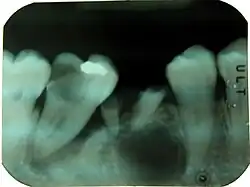

Combined periodontic-endodontic lesions

Combined periodontic-endodontic lesions are localized, circumscribed areas of bacterial infection originating from either dental pulp, periodontal tissues surrounding the involved tooth or teeth or both.[1]